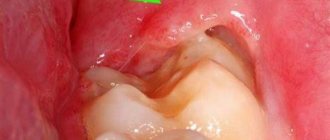

Indications for extraction of jaw units overgrown with gums

Impacted and dystopic wisdom teeth Teeth characterized by the most delayed eruption are known for a host of problems that